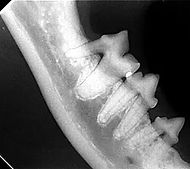

Lesão de

Reabsorção Dentária

Também conhecida como lesão absortiva odontoclástica felina, é uma doença caracterizada por lesões erosivas do esmalte ou cemento, frequentemente situada na porção cervical do dente e classificada de acordo com origem e grau de acometimento, desde lesões superficiais em cemento e dentina, até a exposição pulpar e destruição completa da coroa dentária.